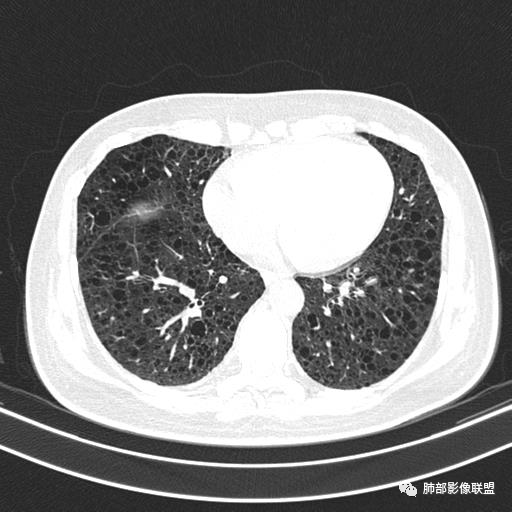

双肺弥漫囊腔,累及肋膈角,囊腔形态相对规则单一。

CT平扫示双肺弥漫分布大小不等囊状薄壁透光区,无内、中、外带分布差异,间质稍示增厚。拟LAM

中年女性育龄期妇女,咳嗽气喘,无吸烟史,有苯吸入史。影像:双肺弥漫均匀小囊腔,无明显分布优势,囊腔形态欠规则,壁薄,部分囊腔边缘血管征,伴双肺弥漫磨玻璃影,无结节,考虑lam,鉴别苯中毒肺损伤,囊腔多有分布优势,小叶中心分布为主,形态规整等

双肺多发大小相近的囊状影,分布趋势趋于一致,中年女性,考虑LAM。部分囊内见血管及分隔影,小叶中心性肺气肿代排

CT表现:双肺弥漫大小不等的薄壁囊腔,囊壁<2mm,外形规则,血管影多位于囊腔周围,囊腔之间肺组织正常,随着疾病进展到晚期,囊腔变大、增多,不可胜数,囊腔可融合成较大的囊,与肺气肿相似,形成间质性肺纤维化。部分病例可出现结节影。